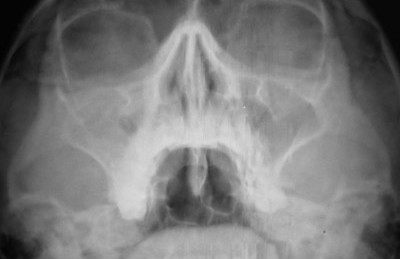

На рентгеновских снимках чаще всего можно увидеть субтотальное затемнение. Затемнение гайморовых пазух обычно появляется в двух нижних третях – обычно это воспаленная слизистая оболочка. Затемнение проявляется обычно при огромном скоплении жидкости или гноя в полости.

Рентгеновская проекция очень четко показывает решетчатые лабиринты, которые забиваются жидкостью наравне с пазухами. На рентгене лучше различается нижняя доля гайморовых пазух.

Носоподбородочная проекция лучше показывает нижние части обеих пазух, чем подбородочная проекция. Решетчатый лабиринт чрезвычайно плохо обозревается при любой проекции.

Затемнение гайморовых пазух выявляется с помощью рентгена и определяется даже врачом-рентгенологом. При появлении тени на снимке врач может предположить гайморит, синусит и прочие подобные заболевания. Рентгенографию назначают для выявления отека, присутствия гнойных масс или воспаления оболочки.

Рентгенограмма показывает наличие посторонних образований в пазухах, и от этого следует наличие какого-либо заболевания.

Пациентка Олеся, 21 год. Девушка пришла в больницу с жалобами на кашель, насморк и затрудненное дыхание, головные боли. Нос был заложен около трех недель. Рентгенография показала субтотальное затемнение гайморовых пазух.

Исходя из результатов обследования, был поставлен диагноз: гайморит (воспаление оболочек гайморовых пазух). Было назначено следующее лечение: Санорин или Тизин, Долфин или Маример, Диоксидин 1% или Хлоргексидин 0,05%.